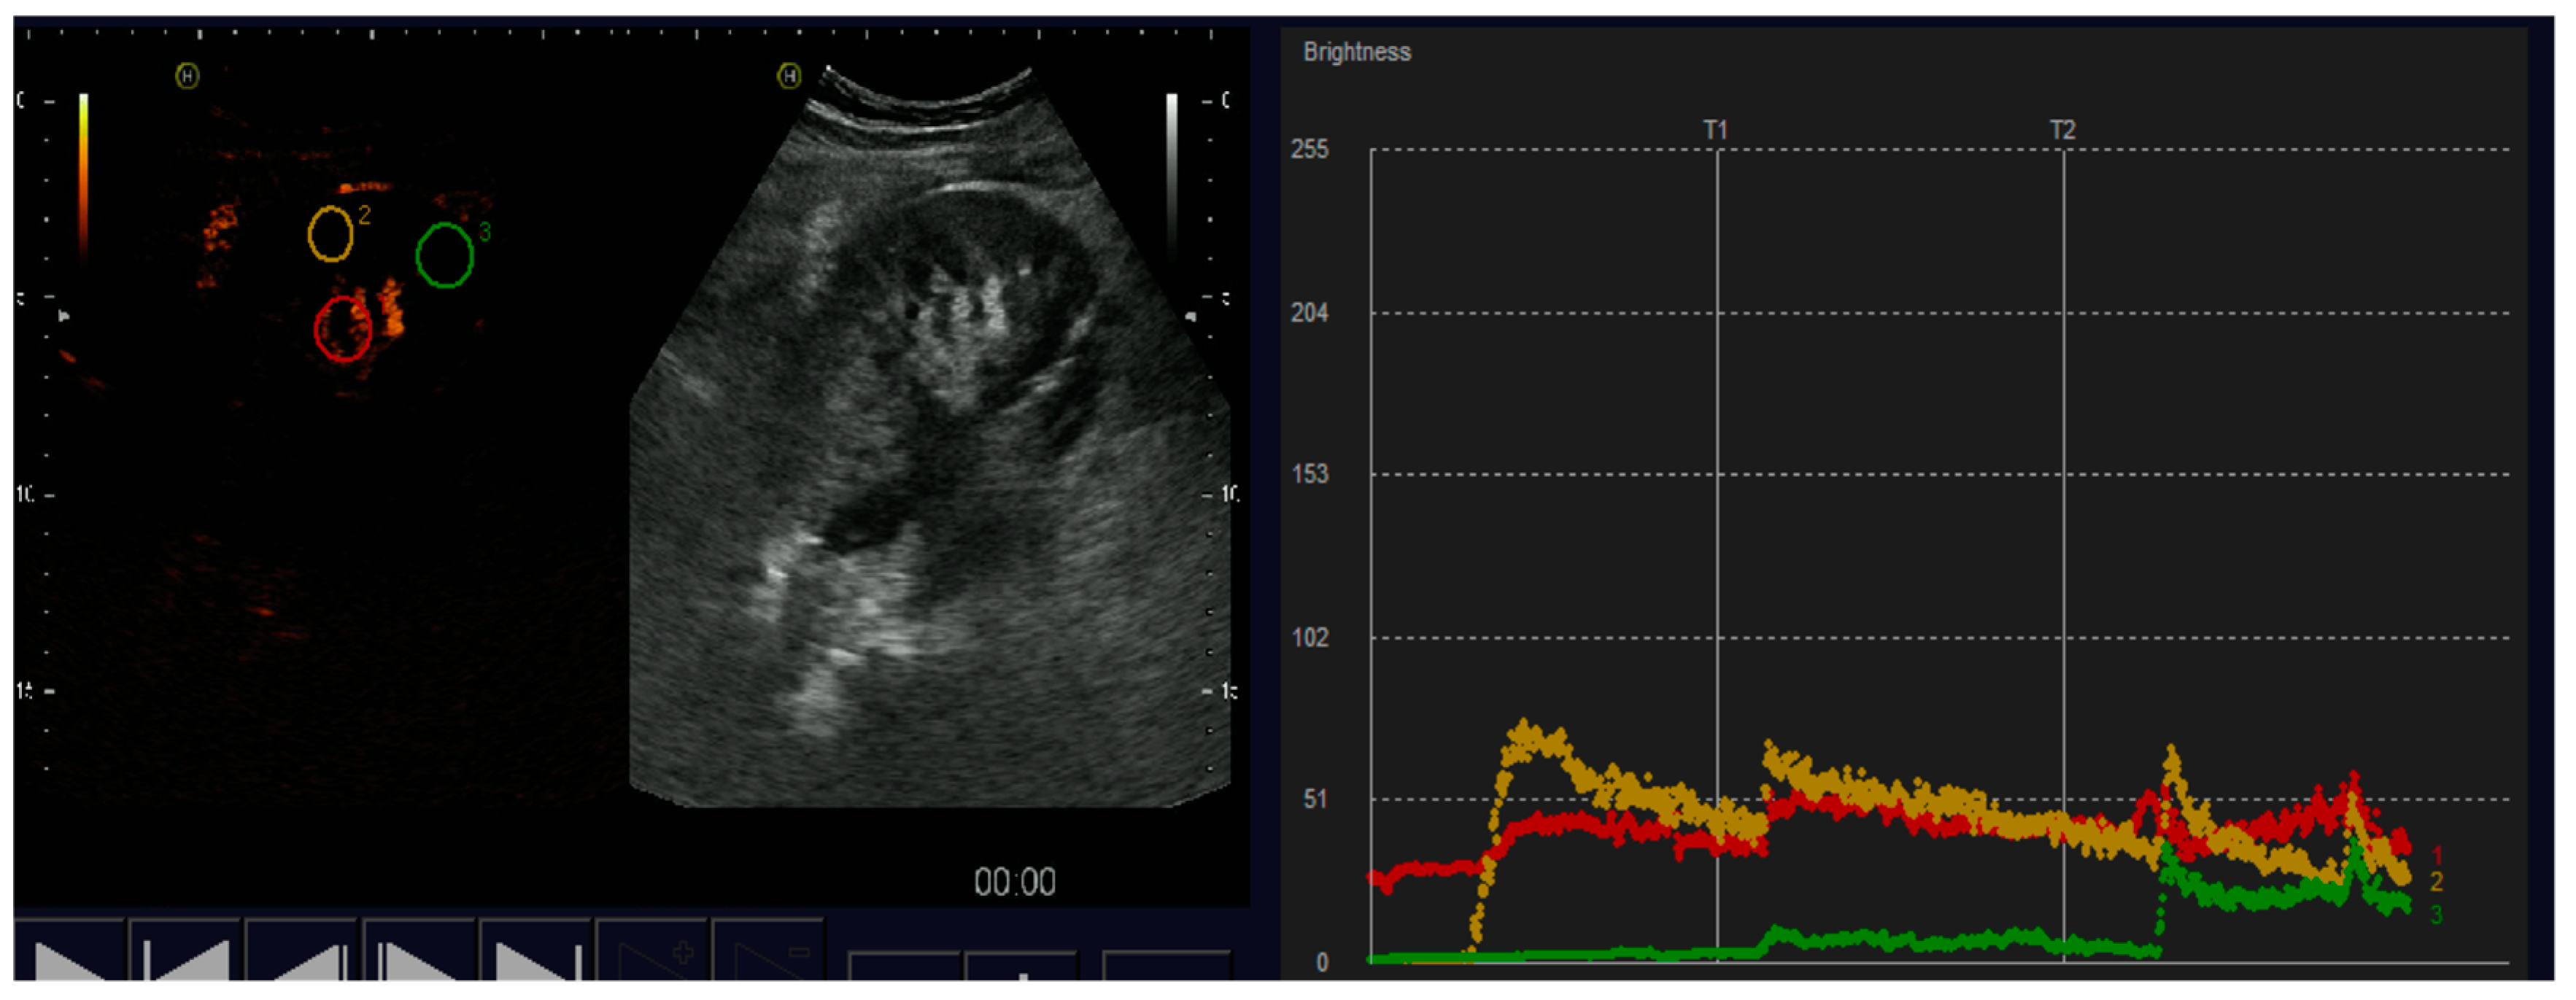

3. Results